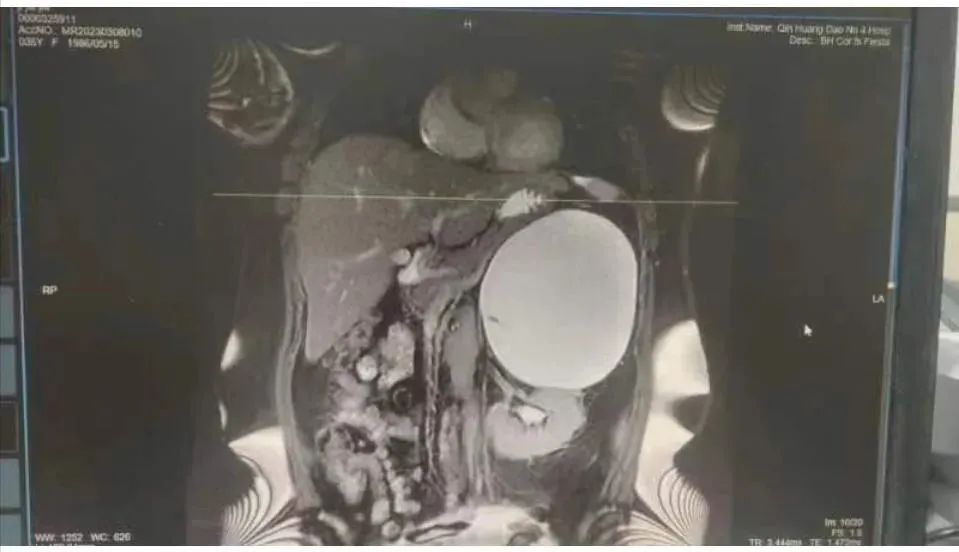

近日,秦皇島市腫瘤醫(yī)院(秦皇島市第四醫(yī)院)外科完成一例巨大腹膜后腫物切除手術(shù)。此前,患者姬女士因咳嗽前往轄區(qū)醫(yī)院就診,經(jīng)CT檢查,發(fā)現(xiàn)脾及左腎之間見一巨大占位,密度不均,約12.3×15.5×9cm3,初步診斷為:腹膜后占位,建議進(jìn)一步檢查。為了進(jìn)一步診治,患者出于對市第四醫(yī)院的信任,來到市第四醫(yī)院就診,門診以“腹膜后腫物”收入院。入院后檢查發(fā)現(xiàn)腫物緊鄰膈肌,患者咳嗽考慮為腫物刺激膈肌所致,頻繁劇烈的干性咳嗽嚴(yán)重地影響患者的正常生活,亟待改善。